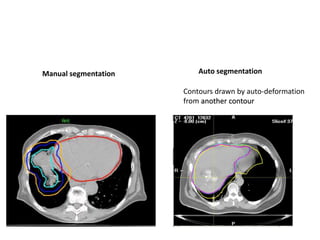

Manual segmentation Auto segmentation

Contours drawn by auto-deformation

from another contour